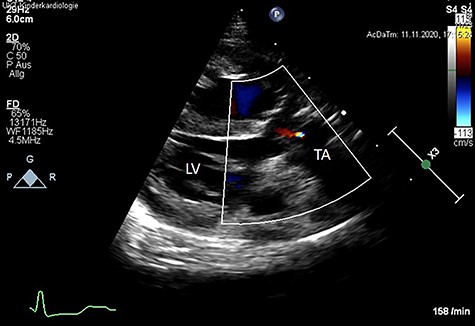

Following surgery, the patient showed a good result and satisfactory recovery. The patient was discharged from the hospital at the third post-operative week. Post-operative echocardiography revealed a good result without TV stenosis or regurgitation (Fig. 3).

Post-operative color Doppler echocardiography (parasternal long axis view) reveals a competent TV with just a minor trace of central regurgitation. Ao: Aorta, LV: left ventricle, TA: truncus arteriosus.